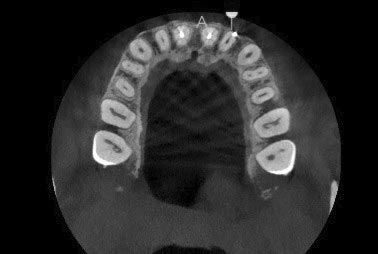

CBCT

En determinados casos, para realizar un diagnóstico preciso y planificar adecuadamente el tratamiento endodóntico, es necesario complementar el estudio radiográfico convencional con una tomografía computarizada de haz cónico (CBCT).

El CBCT proporciona una imagen del diente en tres dimensiones, lo que resulta útil cuando la anatomía es compleja o cuando existen dudas que no se pueden resolver con una radiografía convencional. Nos permite evaluar la presencia de conductos adicionales, calcificaciones, reabsorciones radiculares o lesiones óseas guiándonos a un diagnóstico y tratamiento adecuado.

Esta prueba se solicita únicamente cuando está clínicamente indicada, y resulta especialmente útil en casos complejos, retratamientos endodónticos o cuando existe sintomatología persistente sin una causa clara en las radiografías convencionales.

Aunque en Endodoncia Denia no disponemos de CBCT propio, colaboramos con centros radiológicos y clínicas de confianza, donde el estudio se realiza siguiendo protocolos actuales y con la mínima dosis de radiación necesaria.

El objetivo de solicitar un CBCT es conocer mejor el caso antes de tratar, aumentando las posibilidades de éxito y la conservación del diente a largo plazo.